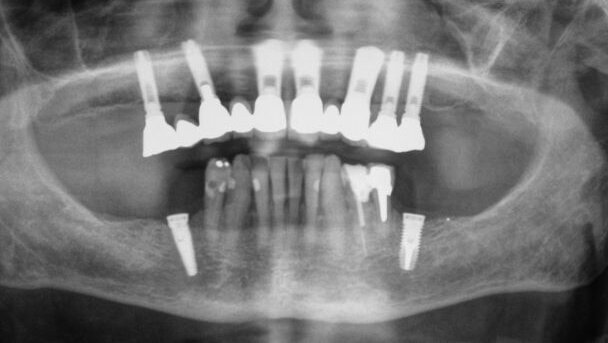

LONDRES, Royaume-Uni : Le nombre de personnes qui choisissent d'avoir des implants dentaires est en augmentation, ce qui a motivé certains experts à examiner les risques potentiels de telles opérations chirurgicales. Ils en ont déduit que ces chirurgies peuvent causer des douleurs intenses et altérer les sensations dans le visage. Une étude récente a montré que les patients sont souvent mal informés par leurs dentistes.

Les chercheurs de l’institut dentaire du King’s College à Londres, ont examiné 30 cas de patients ayant des implants dentaires, qui avaient été dirigés vers une clinique spécialisée en neurologie à l'hôpital du collège.

Parmi les autres recommandations, les chercheurs ont conseillé aux professionnels d’informer les patients de façon adéquate, sur le risque possible de lésions nerveuses permanentes lors de la pose d'implants mandibulaires. En outre, il est nécessaire d’effectuer une planification radiographique préopératoire et un suivi post-opératoire suffisant. Les chercheurs ont également recommandé l'utilisation d'implants courts, afin de réduire le risque de lésions nerveuses, et ont souligné l'importance d’orienter les patients vers un spécialiste sans attendre, si un dommage est constaté.